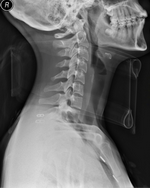

X-ray C Spine With Collar